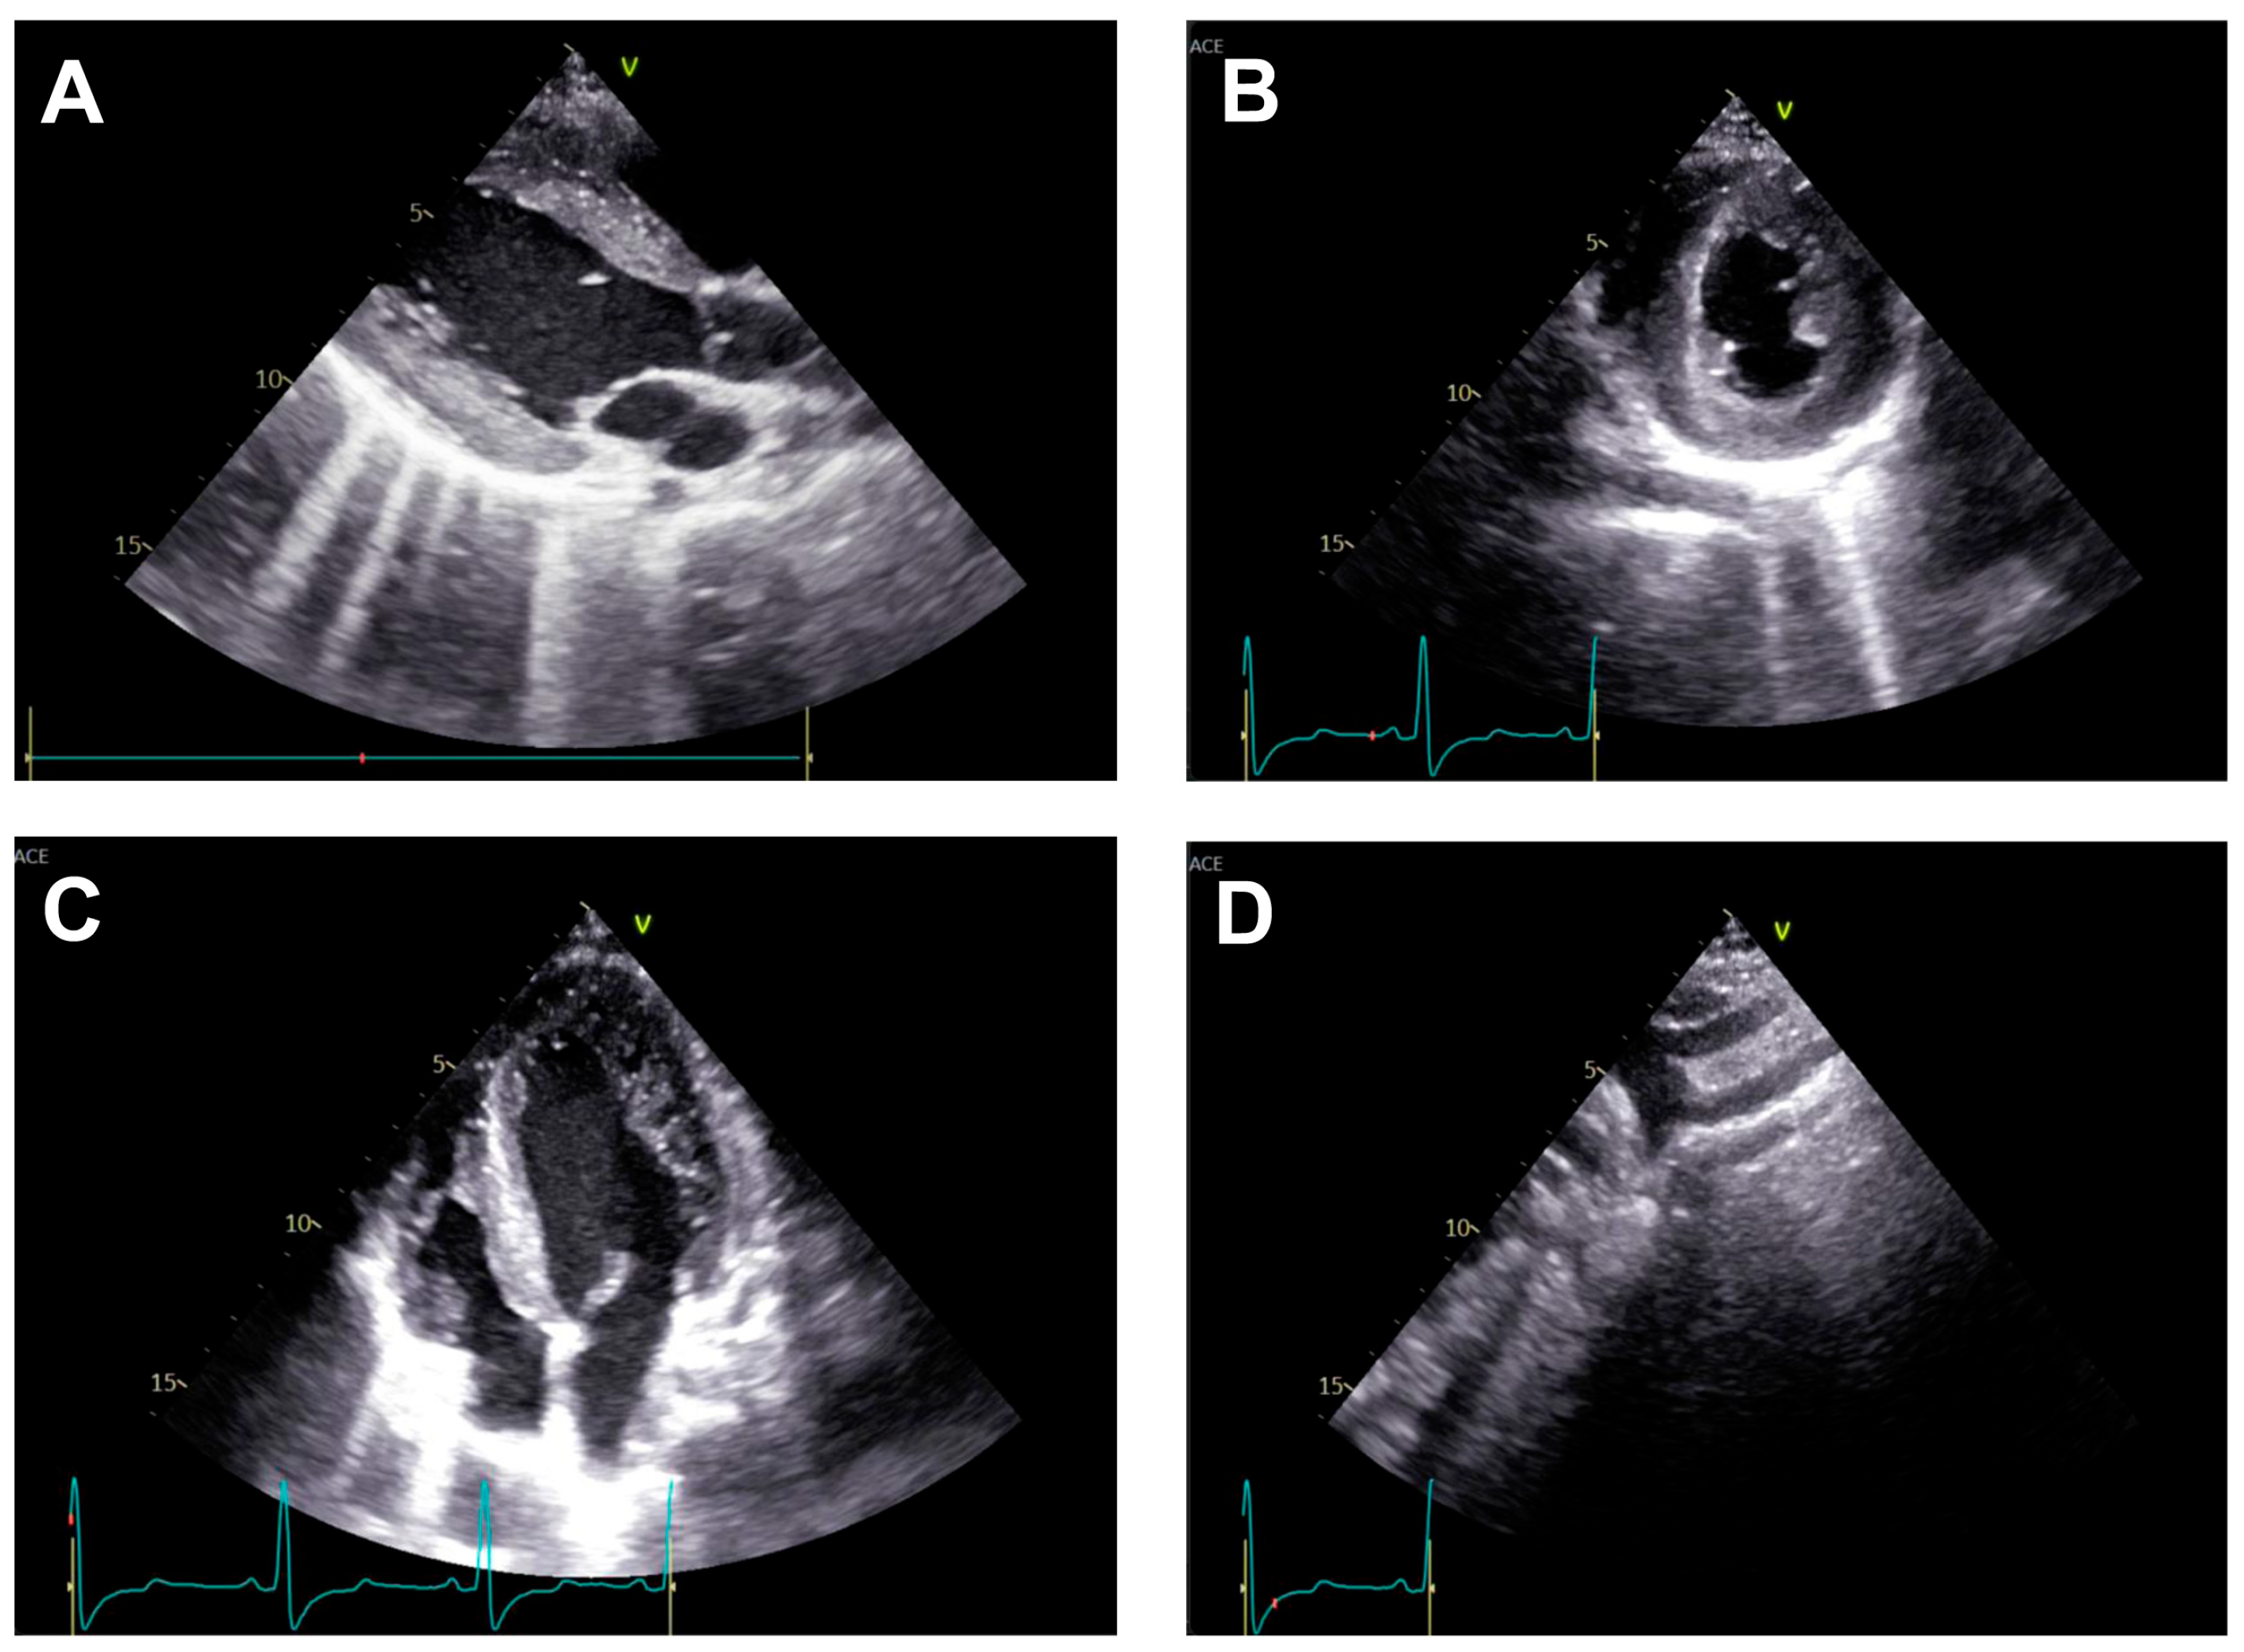

Transthoracic echocardiography (Figure 2) may reveal signs of left ventricular hypertrophy and diastolic dysfunction from the apical and parasternal views, while the suprasternal view may identify the aortic atretic segment. However, the presence of collateral circulation is difficult to identify using this technique [21].

Diagnosis is often incidental, made during workup for hypertension or vascular complaints, and confirmed by imaging (CT—Figure 3, MRI, echocardiography) showing the atretic aortic segment and collateral vessels.